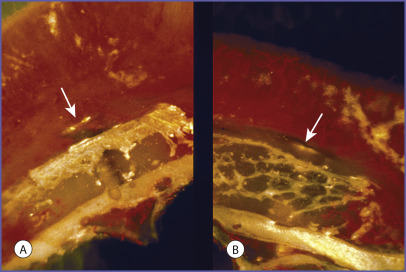

Lin evaluated the volume persistence of calvarial and iliac crest grafts fixed to the rabbit snout with lag screws ( Fig. 3.1 ). Early revascularization of the grafts occurred only in the cancellous portion of both grafts suggesting that the cortical portion of the grafts acted as a mechanical barrier to ingrowing blood vessels ( Fig. 3.2 ). This observation prompted Chen’s study.

Using a model similar to Lin’s, Chen et al. also evaluated the volume persistence of calvarial and iliac crest grafts fixed to the rabbit snout with lag screws. In addition, Chen correlated graft revascularization and graft resorption with graft architecture in the cortical and cancellous regions of both calvarial and iliac grafts. Revascularization was evaluated using latex vascular cast injection, while osteoclastic activity was evaluated using a tartrate-resistant acid phosphatase stain. As expected, he found that at 70 days the calvarial grafts demonstrated greater volume maintenance than the iliac bone (72% vs. 32%, P < .025). He found significantly greater revascularization and osteoclastic activity in the cancellous portion of both the calvarial and iliac crest bone grafts by the 10th day after onlay grafting. Minimal activities were present in the cortical bone ( Figs. 3.3 and 3.4 ). Because calvarial grafts contain more cortical bone, the superior volume maintenance can be understood by the influence of bone architecture on revascularization and resorption. Cortical bone is more slowly revascularized, and therefore less available to osteoclastic activity. The amount of cortical bone in an onlay graft determines its volume maintenance. The importance of graft architecture, as opposed to its embryologic origin, to the volume persistence of onlay bone grafts has been supported in later studies by Gosain.